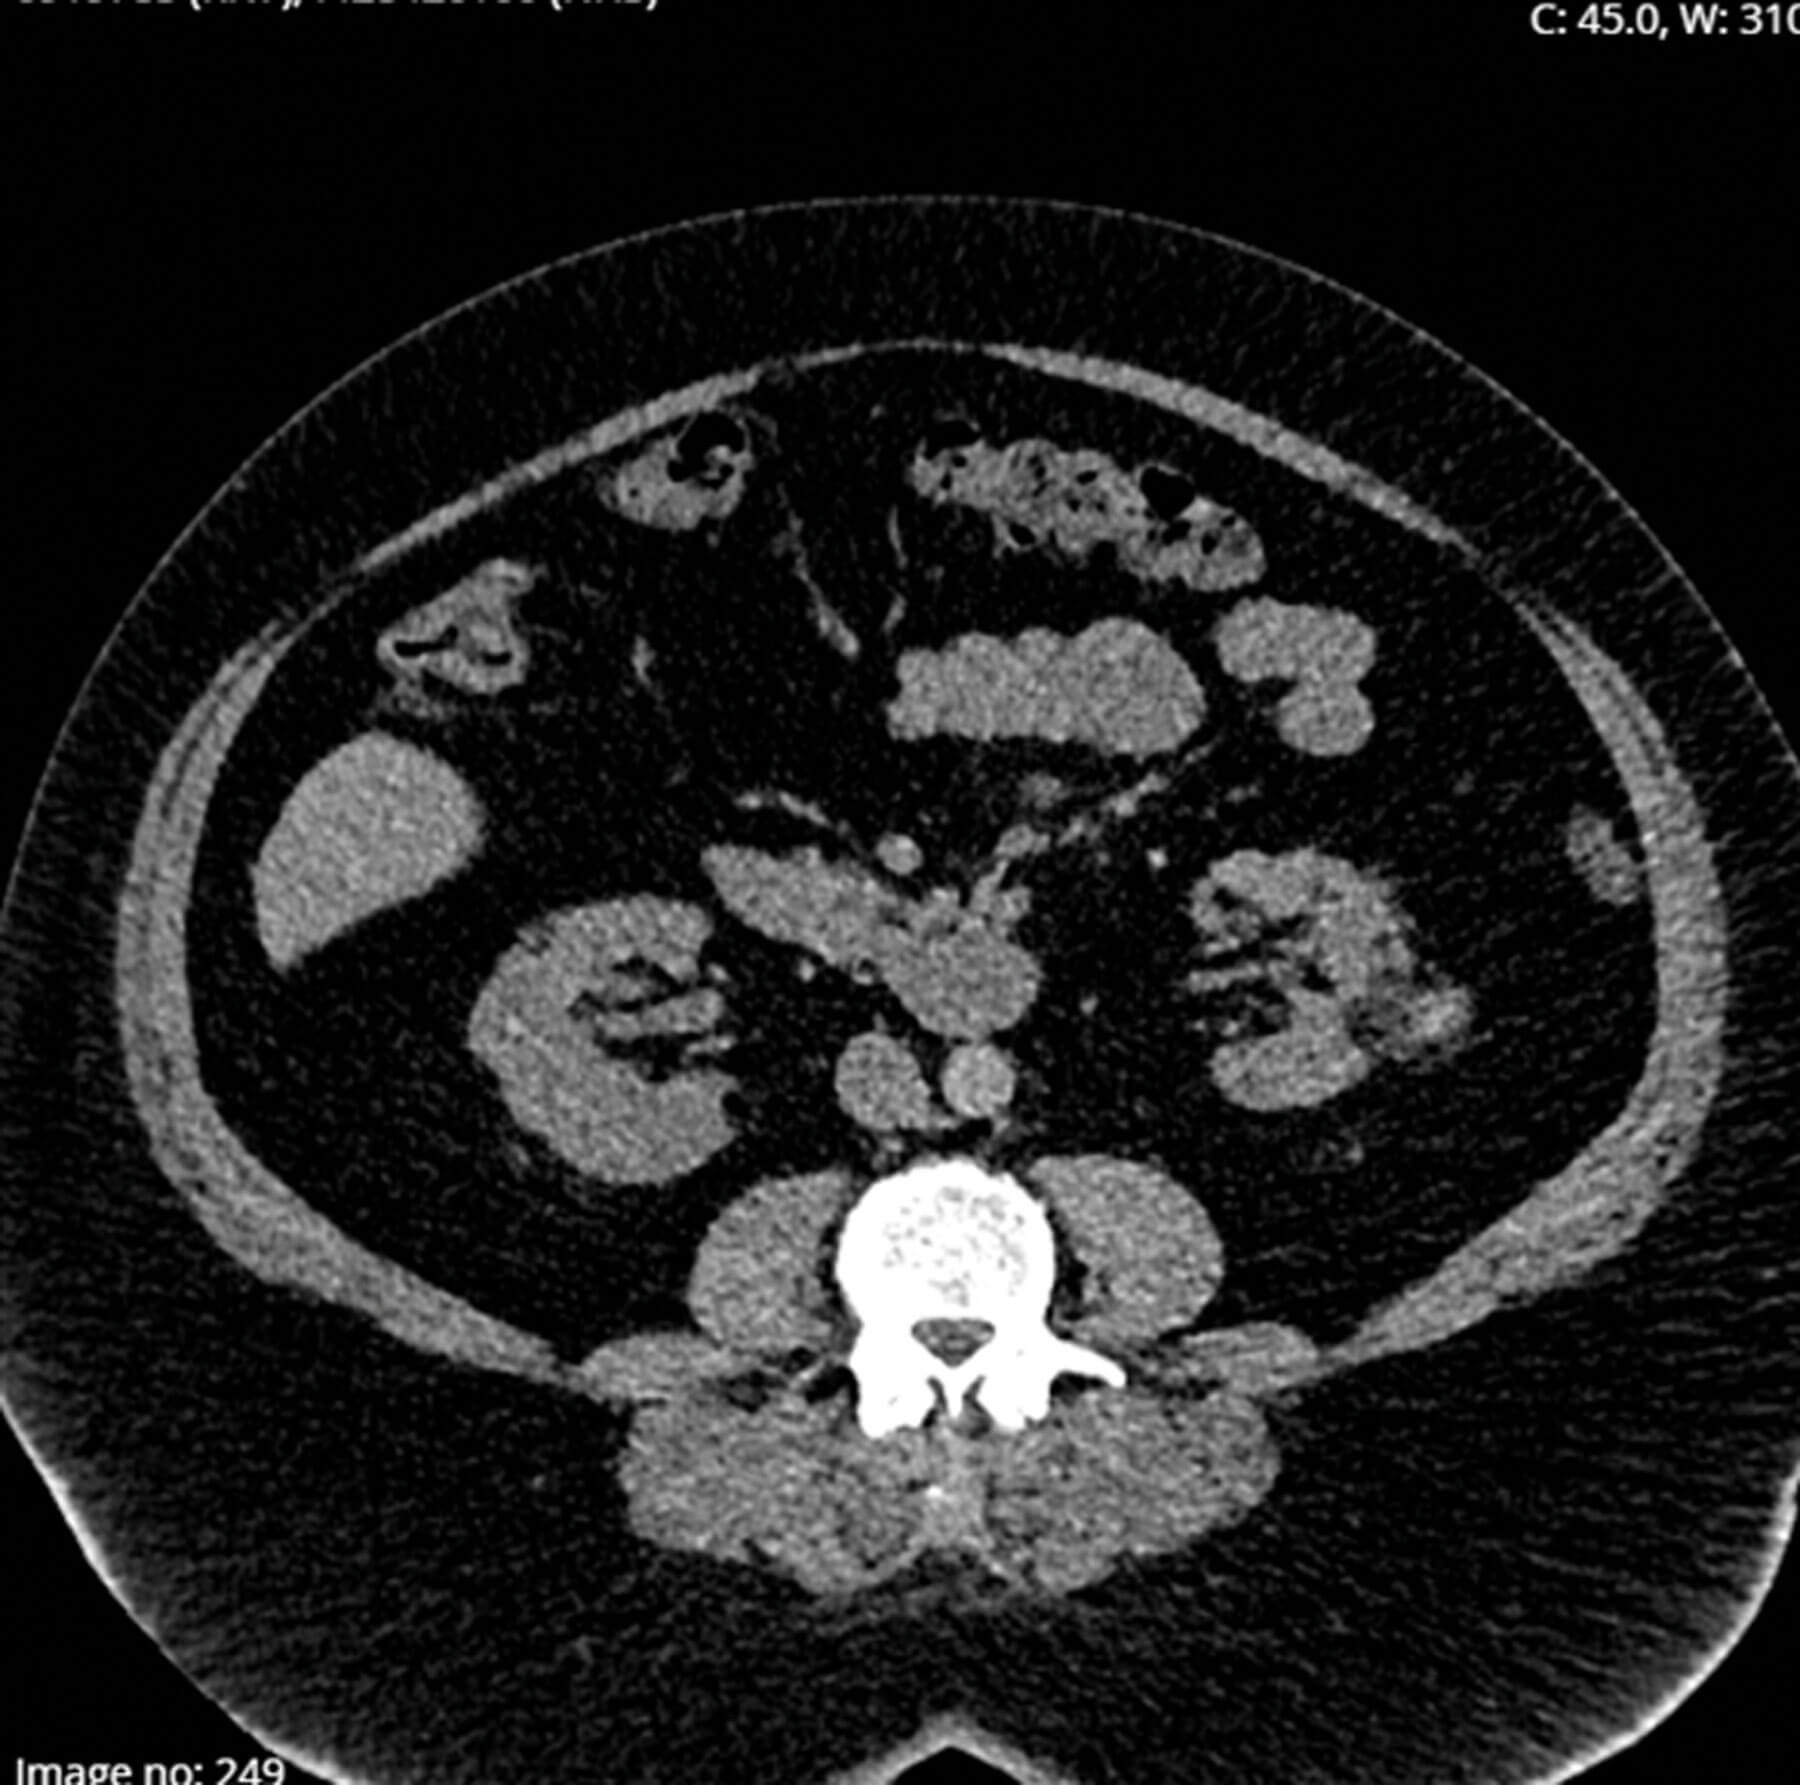

Renal angiomyolipoma (AML) are benign tumours, accounting for approximately 2–3% of all renal neoplasms [1]. Seventy percent of renal AMLs are sporadic, and 20–30% are associated with genetic aetiology. They are composed of smooth muscle, blood vessels, and adipose tissue....